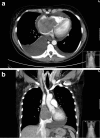

Cardiac metastasis of malignant melanoma: a case report

The heart is regularly involved in metastatic neoplasms with cardiac metastases being found in up to 20 % of autopsies. We present a case about a 42-year-old Caucasian female with a fatal metastatic melanoma to the heart. The five- year survival rate for stage IV melanoma (melanoma with metastases to other organs) is 15 to 20 %. If patients with malignant melanoma present with new onset of cardiac symptoms, clinicians should always be aware of the possibility of cardiac metastases and perform further investigations.